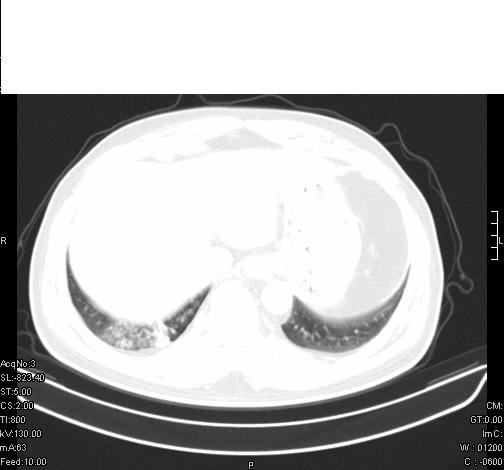

标题: CT6685:右肺阻塞性炎症,增强CT。

前几天,发了患者的平扫片,患者抗炎一周后增强扫描。右中叶病灶吸收明显,但下叶病灶未见明显吸收。右肺门可见结节影,看来凶多吉少

右肺下叶散在的斑片状致密影,下叶支气管变窄。考虑:右肺慢性炎症。

支持:右肺下叶散在的斑片状致密影,下叶支气管变窄。考虑:右肺慢性炎症。

右肺下叶支气管壁不规则增厚,右肺下叶有斑片状影分布。考虑右肺中央型肺癌伴右肺下叶阻塞性改变。建议支纤镜检查。平扫比增强较好显示了病变情况。

既然抗炎治疗有效,可继续治疗;右肺下叶支气管管腔狭窄,管壁增厚,右下肺见斑片状高密度影,右侧主支气管后见结节影(淋巴结?),肺癌不能排出。